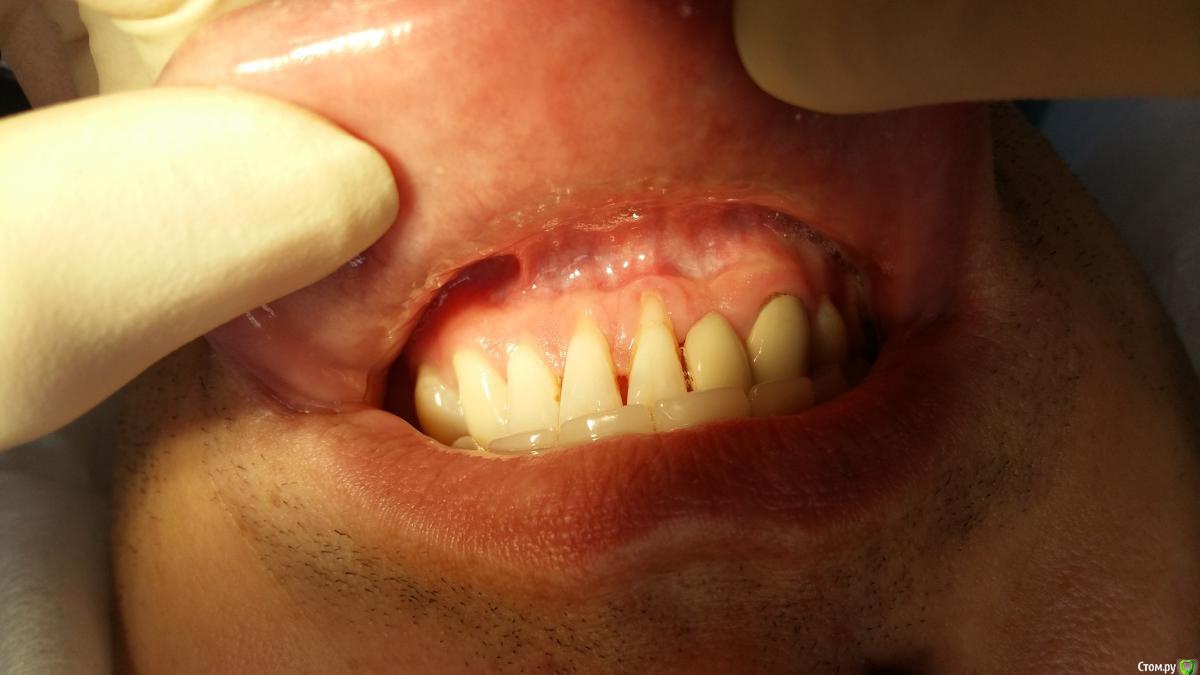

Zubnik7 Опубликовано 24 января, 2017 Автор Поделиться Опубликовано 24 января, 2017 Результат ч/з 3 недели после снятия швов.Был откинут лоскут,коронально смещен,под него в обл 41,31 фиксирован субэпит.трансплантат.стоит ли еще увеличивать зону ЗКПД? Ссылка на комментарий

Zubnik7 Опубликовано 24 января, 2017 Автор Поделиться Опубликовано 24 января, 2017 До операции и после в одном фото Ссылка на комментарий

Д-р Доктор Опубликовано 6 февраля, 2017 Поделиться Опубликовано 6 февраля, 2017 Хороший результат, но думаю кератинизированной нужно ещё чуть-чуть. Ссылка на комментарий

faity Опубликовано 1 марта, 2017 Поделиться Опубликовано 1 марта, 2017 Гигиена страдает. Снимите швы- отправьте к гигиенисту недели через 2-3 Ссылка на комментарий